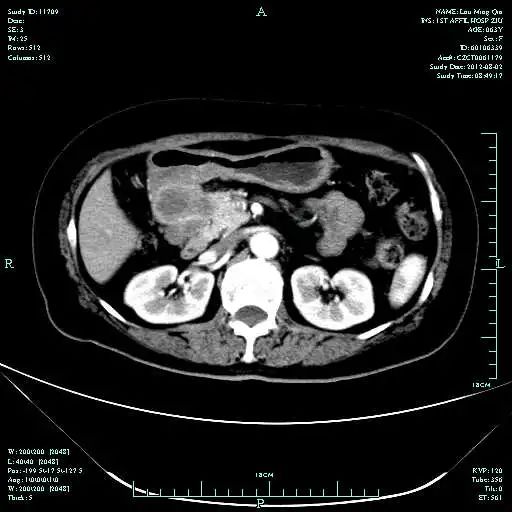

CT-T

CT-H1

影像学检查结果评估:cPD。

疗效评估:cPR

TOGA研究是第一个使用HER2抑制剂曲妥珠单抗治疗不能手术的局部晚期、复发或转移的HER2阳性胃癌患者的Ⅲ期临床研究。TOGA研究结果显示,IHC2+/FISH阳性或者IHC3+的患者与对照组相比,OS分别为16.0个月和11.8个月(HR为0.65)。曲妥珠单抗联合化疗显著提高了HER2阳性晚期转移性胃癌的治疗缓解率和总体生存率。2012年8月,曲妥珠单抗治疗HER2阳性转移性胃癌适应症在我国获批。对该患者进行病理切片会诊,幸运的是其HER2检测为阳性。随即进行靶向联合化疗治疗,三个周期后,肝转移灶消失,曲妥珠单抗治疗效果显著。九个周期的靶向治疗联合放化疗后,疗效评估cPR,随即行手术治疗。